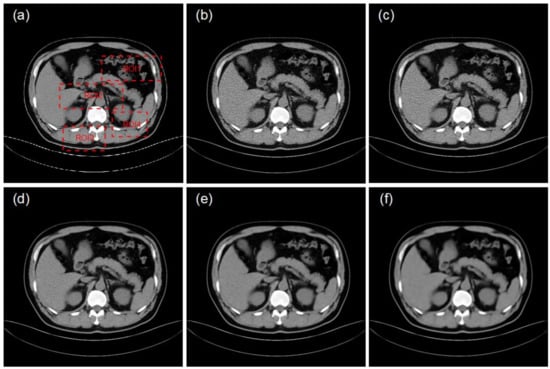

4.2. Clinical Data Experiments

| ROI | LDCT | Bicubic | RFSR | RFSR 2nd | RFSR 5th |

|---|---|---|---|---|---|

| 1 | 20.55 | 25.76 | 35.89 | 36.97 | 34.01 |

| 2 | 21.33 | 26.13 | 35.97 | 37.01 | 34.03 |

| 3 | 22.31 | 27.43 | 36.12 | 37.09 | 34.09 |

| 4 | 22.06 | 26.54 | 36.45 | 37.63 | 34.61 |

| 1 | 0.71 | 0.79 | 0.90 | 0.92 | 0.86 |

| 2 | 0.74 | 0.81 | 0.92 | 0.95 | 0.88 |

| 3 | 0.78 | 0.83 | 0.91 | 0.94 | 0.87 |

| 4 | 0.76 | 0.82 | 0.89 | 0.93 | 0.85 |